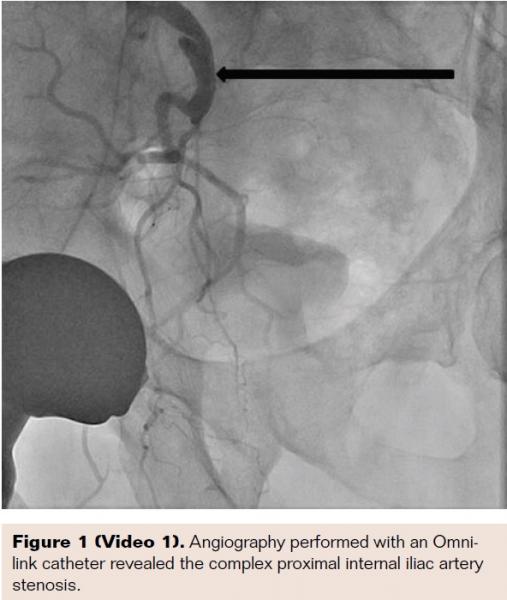

A 78-year-old active physician presented with right thigh and buttock claudication and impotence. Prescription erectile dysfunction (ED) medications were ineffective for the impotence. He was evaluated by primary care and found to have a normal testosterone level. The patient was a previous smoker, and also had hyperlipidemia and had a left anterior descending stent placed 13 years prior to this visit. He underwent right groin abdominal and long leg run-off. In addition to bilateral anterior tibial 100% occlusion, he had a subtotal proximal internal iliac artery complex 90% stenosis. Measurement of the gradient revealed a 60 mm drop across the lesion. A 6 Fr Destination sheath (Terumo Corporation) was placed and the lesion was crossed with a Cougar wire (Medtronic). We predilated the stenosis with a 5 x 20 mm Armada balloon (Abbott Vascular). We then placed a 7 x 19 mm Omnilink stent (Abbott Vascular). Unfortunately, in spite of the predilation, the stent didn’t fully cover the complex stenosis; this may have been due to the “watermelon seeding” effect. We therefore placed an 8 x 29 mm Omnilink stent, which resolved the stenosis. The gradient was reduced to zero.